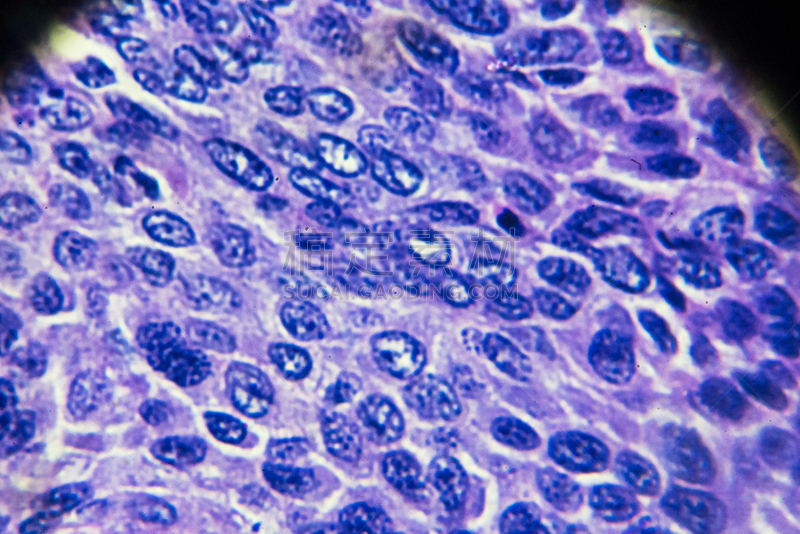

人类平滑肌肉瘤详情